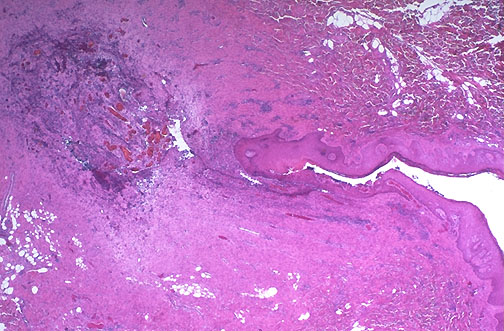

| Here is a pilonidal sinus and tract extending to skin surface at the right. A pilonidal sinus appears as a small opening, sometimes with protruding hair, in the intergluteal fold several centimeters posterior to the anus. These lesions are most common in young caucasian males. |